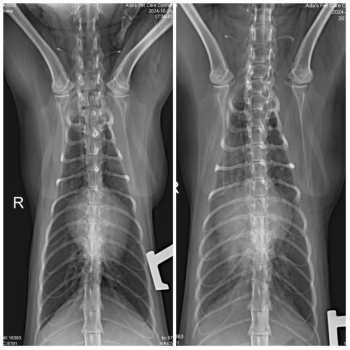

首先,我们进行了胸部X光检查,发现肺部出现弥漫性密度增高的现象,这可能是肺部积水的信号,也提示可能存在心脏问题。此外,X光片还显示了支气管征象,心脏轮廓不清晰,暗示着心脏可能存在增大或其他异常情况。